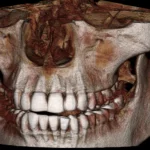

Cone Beam Case Study:  Abscess on #24